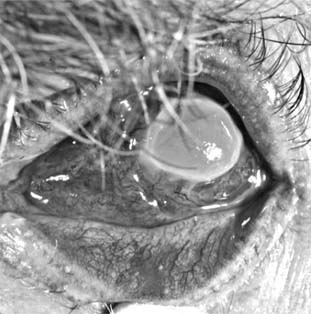

Unlike recurrent HSV keratitis that usually affects only the epithelium, VZV keratitis affects the stroma and anterior uvea at onset. The epithelial lesions are blotchy and amorphous except for an occasional linear pseudodendrite that only vaguely resembles the true dendrites of HSV keratitis. Stromal opacities consist of edema and mild cellular infiltration and initially are subepithelial. Deep stromal disease can follow with necrosis and vascularization (Figure 6-6). A disciform keratitis sometimes develops and resembles HSV disciform keratitis. Loss of corneal sensation is always a prominent feature and often persists for months after the corneal lesion appears to have healed. The associated uveitis tends to persist for weeks or months, but with time it eventually heals. Scleritis (sclerokeratitis) can be a serious feature of VZV ocular disease.

Figure 6-6

Figure 6-6: Herpes zoster keratitis.